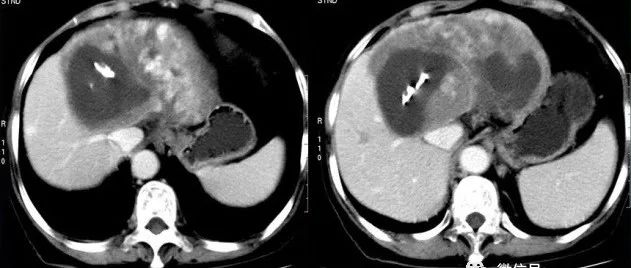

老年女性,右上腹胀痛不适半年余,请诊断!

医学影像  yxyx-app  医学影像APP,打造伴随医生快速成长的影像学习社区。与影像园(Xctmr.com)一起提供最全面的影像案例库、基础(解剖、病理、影像诊断)知识、影像技术及考题等,为医生提供最佳的医学影像参考。【所属科室】消化科【基本资料】患者,女,75岁【主诉】右上腹胀痛不适半年余【影像图片】【讨论问题】如何诊断?【医学影像APP用户讨论】评论:...

医学影像APP 2022-07-04